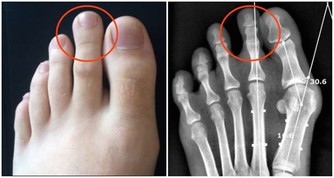

專家表示,千萬不要小看濕疹,若不規範治療,將急癢難耐,逼得患者抓的遍體鱗傷,滲液、乾燥、流血、結痂、粗糙肥厚與裂口,瘙癢變成鑽心的癢,夜裡難以入睡影響日常的生活。而濕疹出現的最常見部位一般在四肢及腰部,尤其以下肢最為明顯。

好發的部位是皮膚油脂分泌最少的小腿前側以及腰部附近。

嚴重時可能還會造成皮膚潰爛、皮膚增厚現象,所以不可不慎。